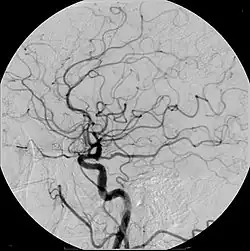

Iodine (circulatory system)

An iodine-based contrast in cerebral angiography

Iodinated contrast contains iodine. It is the main type of radiocontrast used for intravenous administration. Iodine has a particular advantage as a contrast agent for radiography because its innermost electron ("k-shell") binding energy is 33.2 keV, similar to the average energy of x-rays used in diagnostic radiography. When the incident x-ray energy is closer to the k-edge of the atom it encounters, photoelectric absorption is more likely to occur. Its uses include: